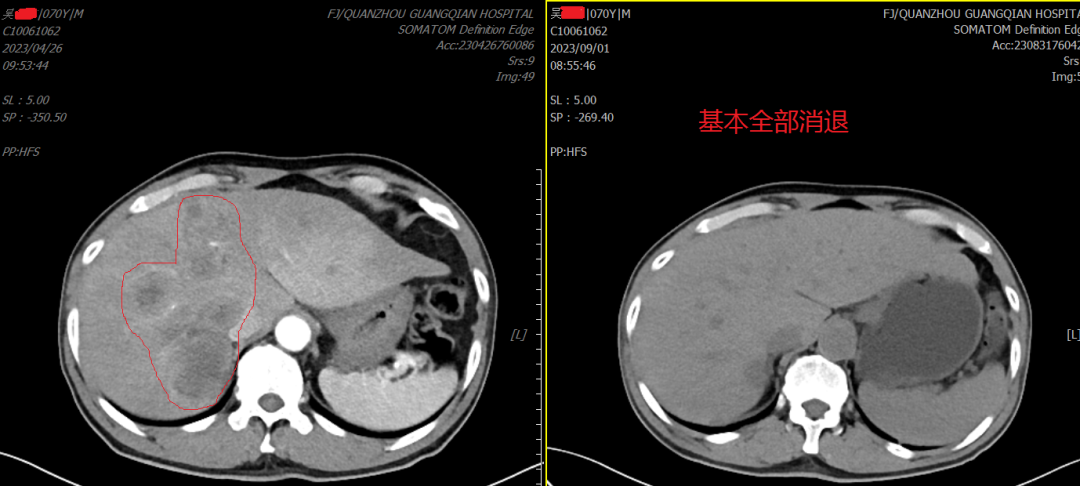

下圖是我院腫瘤放療一區(qū)梁德川副主任醫(yī)師、林劍輝醫(yī)師在浙江省腫瘤醫(yī)院花永虹、姜鋒教授指導(dǎo)下完成的對吳阿伯多發(fā)肝轉(zhuǎn)移治療效果圖……